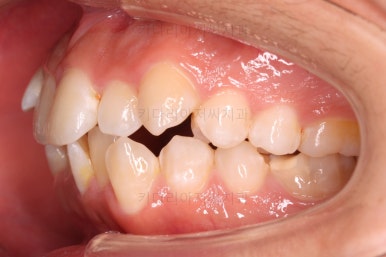

초진 시 입안의 모습입니다.

앞니가 많이 삐뚤고, 송곳니가 부각되어 덧니처럼 보이네요.